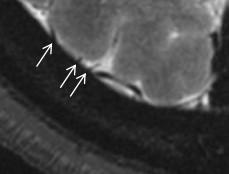

Hanneman, 2015 “tadpole sign”

 Choudharyetal, 2015

 “lollipop” sign

Use of T1 COR Vasc to confirm rupture of bridging vein…

 Bridging vein injuries in shaken baby syndrome : Forensicradiological metaanalysis with special focus on the tadpole sign].

 Wittschieber et al, 2021

 No full rupture but often just “injured”…most literature now looks at high resolution gradient imaging

“Venous Injury” on MRI… using high resolution gradient imaging in AX and COR planes

Normal 9-12 major (50 total) bridging veins will traverse the hygromas, along with additional smaller veins…

If see “susceptibility” along the vein, may be acute or chronic injury.